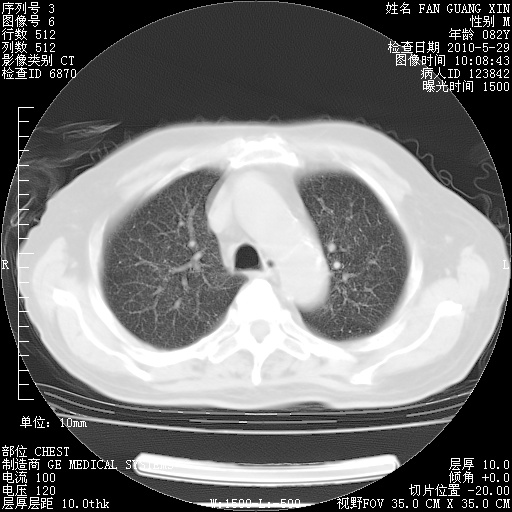

再治疗10天后的肺部CT

再治疗10天后的肺部CT 纵膈窗

阅读此次胸部CT,肺间质渗出性改变较入院时有吸收。目前从体温、白细胞、中性分叶明显增高,肯定存在细菌感染(发生医院感染哦,若无消化道及泌尿系统等感染的依据,肺部感染可能大)。若你院头孢哌酮舒巴坦钠耐药率较高,同意你的方案,若48小时体温仍高,可考虑使用碳青霉稀类抗菌药物,同时可予超声雾化、注意滴数时加大液体量。白蛋白33.30g/L较低哦,需加强营养等支持治疗。